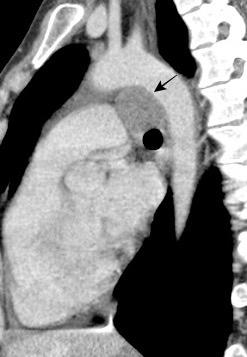

Anatomía

BPI: 75% de normales

La imagen es probable que represente al BPI, a la altura del nacimiento del BLSI.

AV,. The left lateral radiograph of the chest. Part One. Med. Radiogr. Photogr.1979.

La presencia de tumor o ganglios rodeando el BPI hace que este aparezca como mucho más nítido y definido.

Carcinoma microcítico..

Parálisis frénica. Atelectasia parcial de LSI.

Whitten CR. A Diagnostic Approach to Mediastinal Abnormalities. Radiographics 2007 / Marano R et al. Cardiac Silhouette findings And mediastinal lines and stripes. Chest. 2011

En el normal, el bronquio intermediario (BI) aparece en la proyección lateral, como una línea fina vertical que cruza el bronquio del LSI en su unión con el principal. (BPI) Engrosamiento del bronquio intermediario (BI)

97% de normales

Causas

Fallo cardiaco

Ca de pulmón

Metástasis

Linfoma

Sarcoidosis

Castleman

Schnur MJ et al.. Thickening of the Posterior Wall of the Bronchus Intermedius. Radiology. 1981

MJ et al.. Thickening of the Posterior Wall of the Bronchus Intermedius. Radiology. 1981 Ca. microcítico